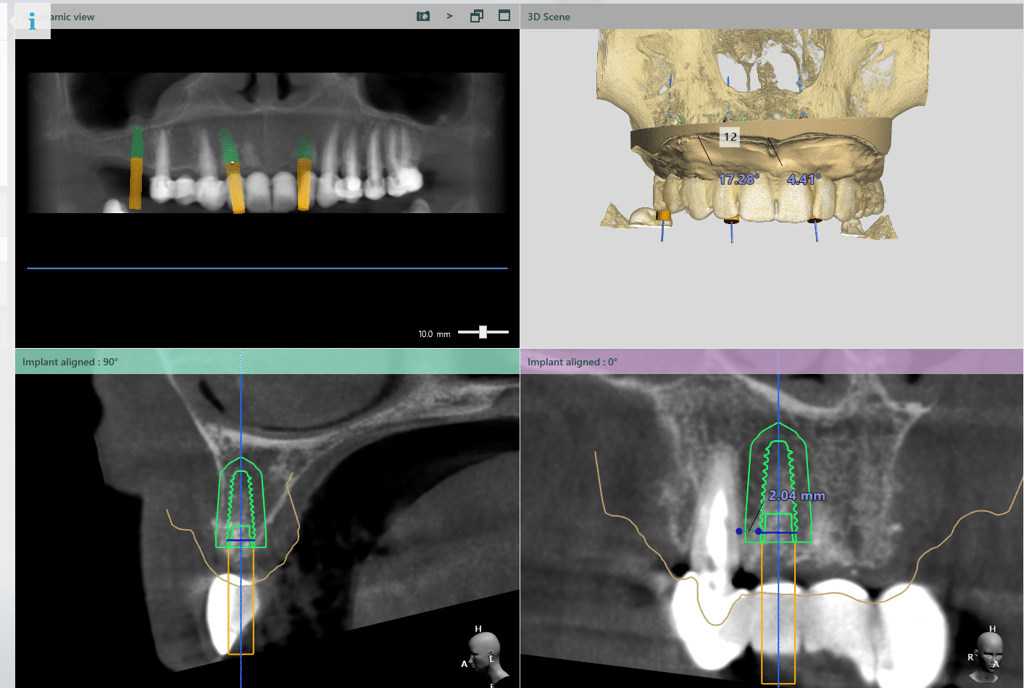

Implanturile vor fi inserate cu ghid chirurgical după 6 luni. Se vor insera implanturi în pozițiile 12, 22, 16, 36, 46.

S-a realizat scanarea digitală a arcadelor și ocluzia pacientului, iar împreună cu tehnicianul radiolog de la DigiRay, Dr. Eliza Drăgan a efectuat în software-ul 3Shape suprapunerea fișierului .stl al amprentei digitale peste fișierul .dcm de la CBCT. Medicul a planificat individual poziția și axul de inserție al fiecărui implant.